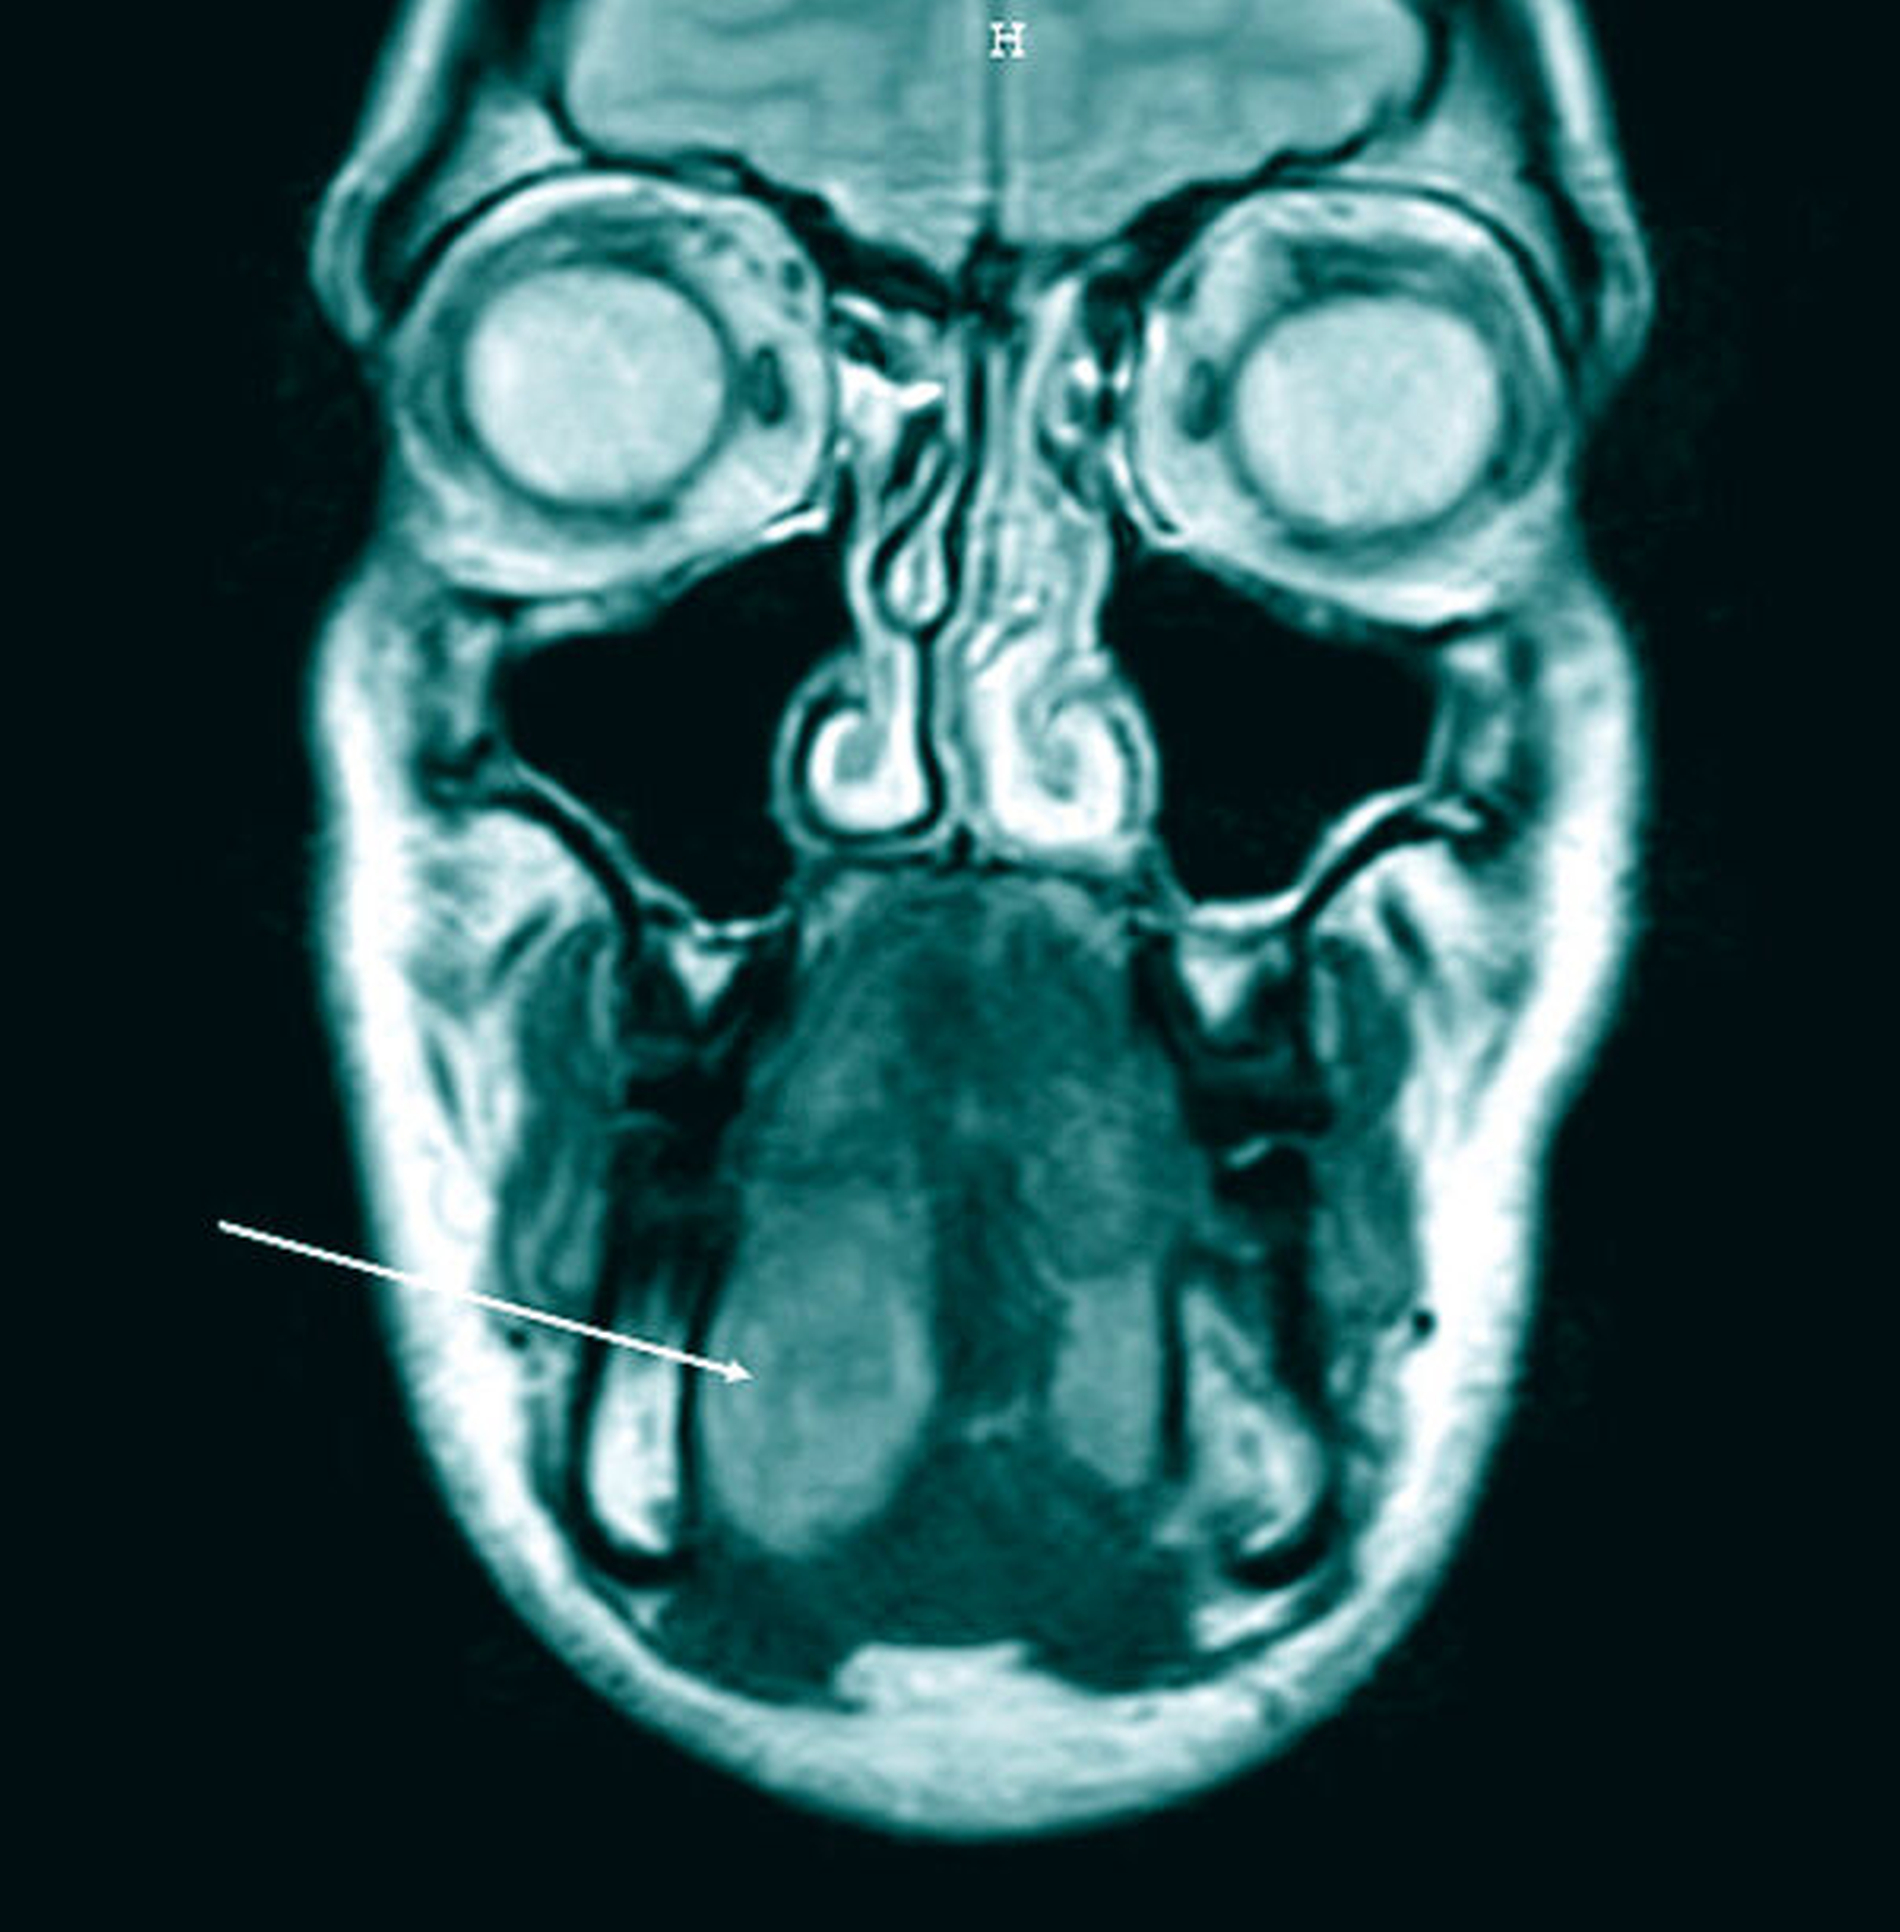

Zur weiteren Diagnostik erfolgte eine Magnetresonanztomografie (MRT). Diese zeigte eine glatt begrenzte, heterogene Raumforderung der Glandula sublingualis rechts (33 mm x 31 mm x 20 mm) mit Verdrängung der umgebenden Strukturen ohne Infiltration (Abbildungen 1 und 2). Es wurde die Verdachtsdiagnose eines pleomorphen Adenoms der Glandula sublingualis rechts gestellt. Weiterhin wurde eine deutlich atrophierte Glandula submandibularis rechts beschrieben.